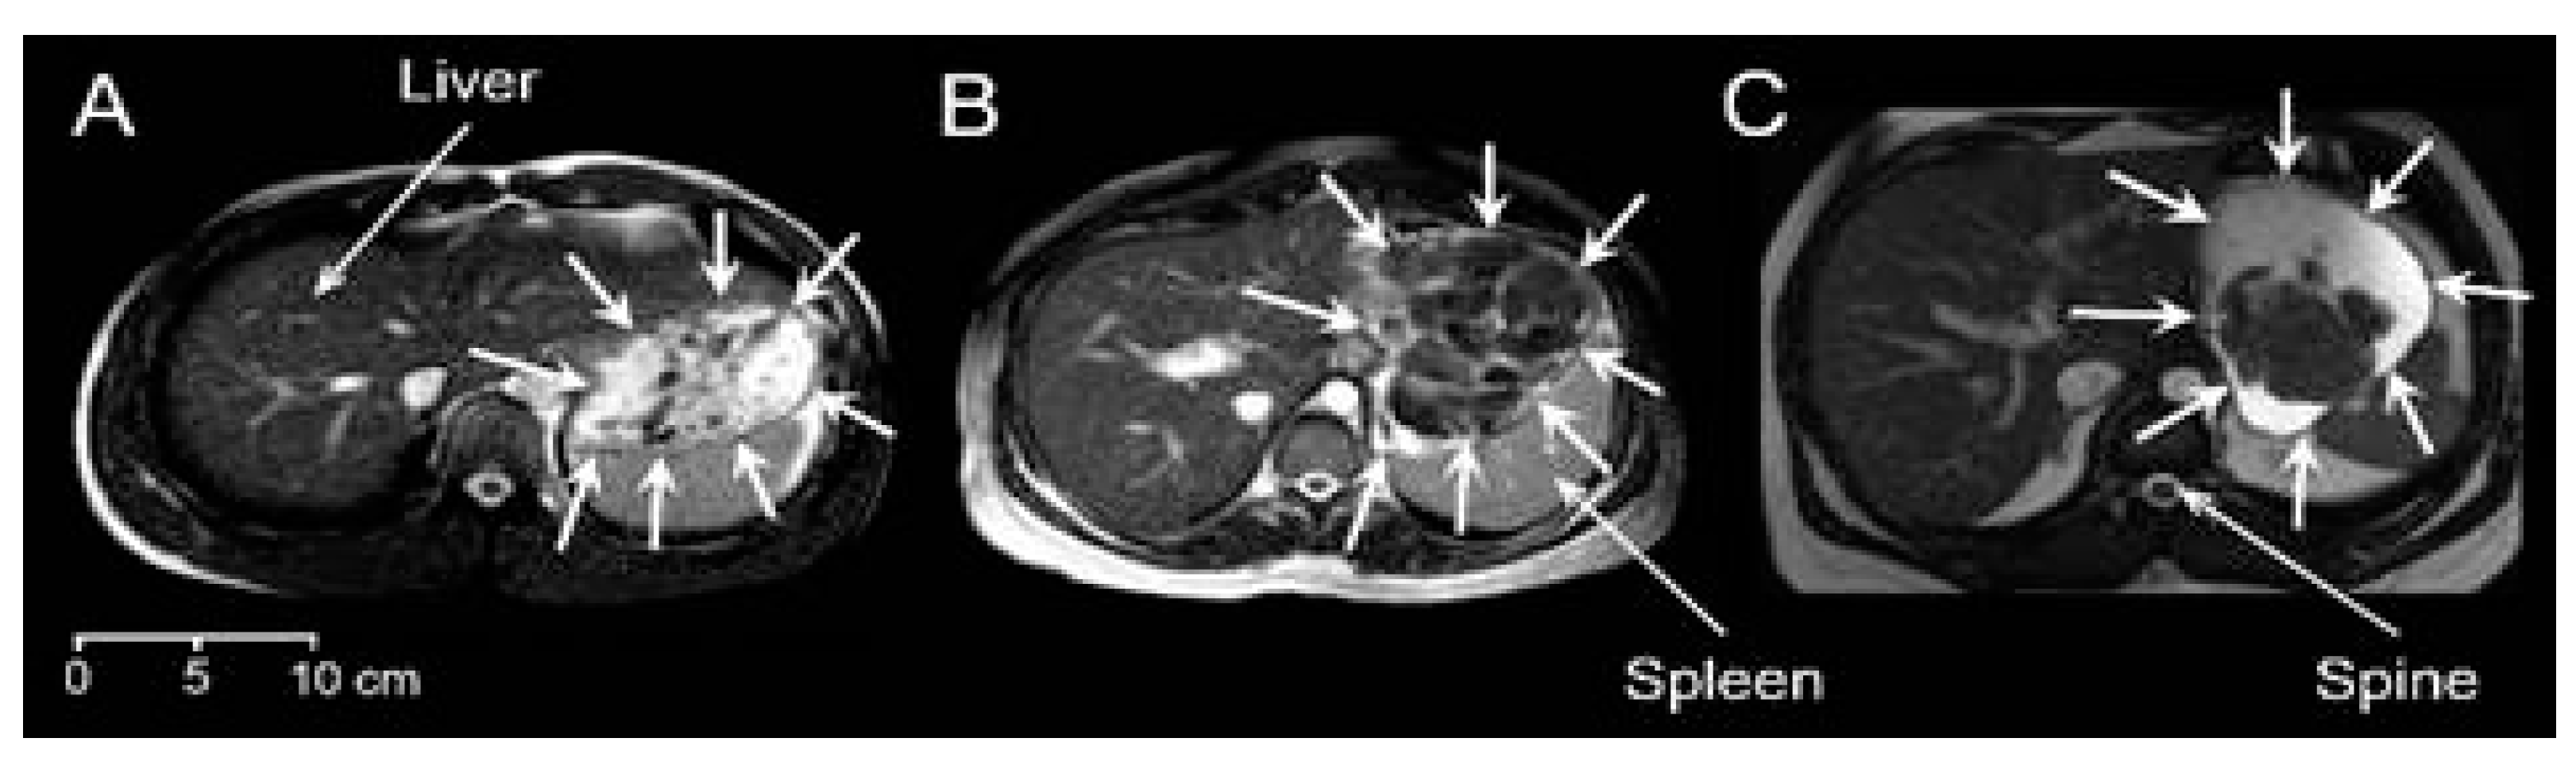

Good-quality images were obtained from all participants. There was a variety of different visual appearances, types and shapes of food boluses in the stomach. Figure 1 shows an example for each meal. In this type of MRI image weighting, fluids in the stomach appear bright and solids appear dark. Meal 1 showed a distribution dispersed in the stomach, comprising principally smaller boluses surrounded by fluid, but also larger boluses of heterogeneous appearance. These appeared to be clumps containing multiple smaller boluses, possibly containing different components of this chicken and vegetable mixed meal, formed in the mouth and upon swallowing. These larger boluses appeared mostly in the proximal stomach. Gravity seemed to play a part too with the smaller boluses often seen at the top of the stomach. More homogeneous chyme of a brighter appearance, suggesting increased hydration, could be seen in the distal antral region for Meal 2, whilst separate or sometimes clumped together bread boluses were located more proximally in the body region of the stomach. These were larger boluses with a lower amount of surrounding fluid. Finally, the content of the stomach of those who ingested Meal 3 resembled a phase separation. Large boluses were seen located close to each other and in the bottom part of the stomach due to the gravity effect, noting that participants were in supine position.

Figure 1. Example axial MRI images for the three different meals. (A) Meal 1: chicken and vegetables. (B) Meal 2: bread. (C) Meal 3: cheese and yogurt. The liver, spleen and spine anatomical landmarks are indicated, and the stomach boundaries are indicated by surrounding white arrows. In this type of MRI image weighting, fluids in the stomach appear bright and solids appear dark.